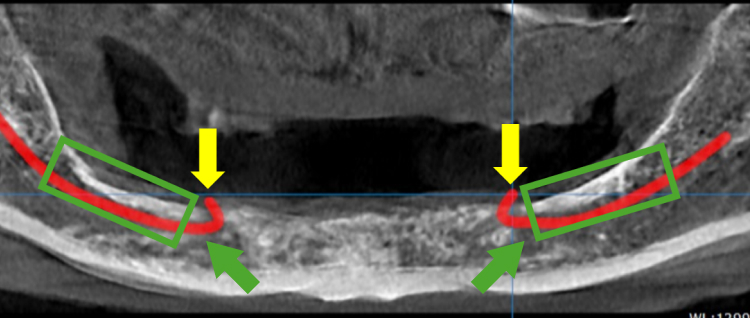

• 엑스레이 촬영결과 작은 어금니쪽에 신경이 돌출되어

틀니가 신경을 눌러 통증이 발생된 상태

• 큰 어금니 쪽 치조골이 너무 얇아서

신경 손상 부작용이 발생할 위험이 있음

All On 5로 임플란트 식립 결정!

노란박스 부분에 5개의 임플란트를 식립하고

고정성 보철을 연결해서 전체 치아를 회복합니다

네비게이션 임플란트의 가이드를 통해

식립 위치를 모의 수술 후 안전하게 식립합니다